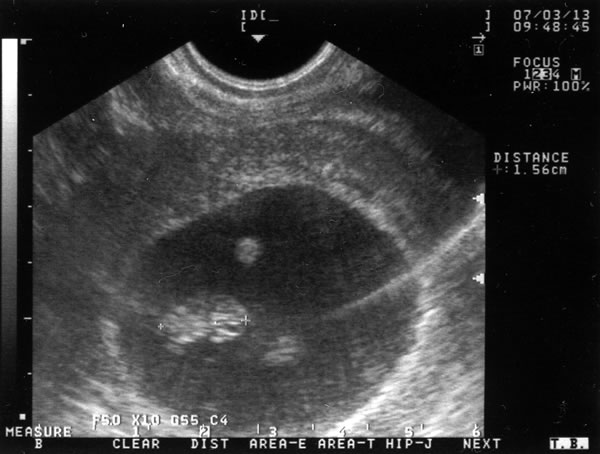

診断時に撮ってもらったエコー。

小さな命はちょっとずつですが、大きくなっています。

ただ今1.56cm・・・

ちっさいなぁ、爪の先くらい・・・ですか?